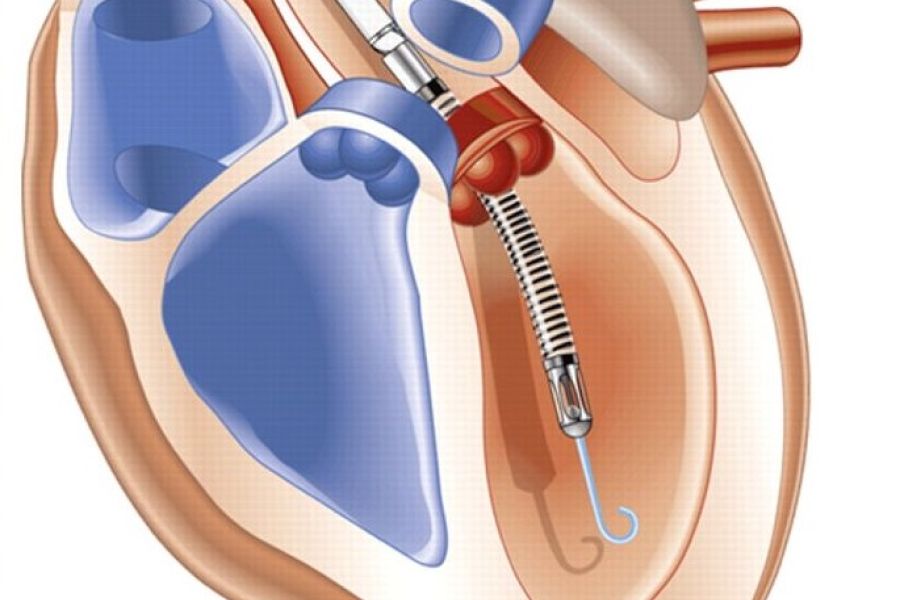

Nieuwe hartklep via lies biedt hoop voor patiënten zonder alternatief

Europese primeur voor Catharina Ziekenhuis Het Catharina Ziekenhuis heeft een Europese primeur: de eerste plaatsing van een nieuwe mitralisklep via de lies. Het zorgt voor patiënten die nu wel uitzicht hebben op een toekomst terwijl ze eerst uitbehandeld waren. Het Hart- en Vaatcentrum van het Catharina Ziekenhuis heeft opnieuw een belangrijke stap gezet in de […]

Nieuwe hartpomp in VieCuri biedt patiënten voordeel bij risicovolle dotterbehandeling

Klein van stuk, groots in werking: de Impella. Deze innovatieve pomp kan tijdelijk de functie van het hart overnemen tijdens een risicovolle dotterbehandeling. Sinds kort zetten de interventiecardiologen van VieCuri deze techniek in, waardoor patiënten voor deze ingreep niet meer naar Maastricht of Eindhoven hoeven te reizen. Per jaar behandelt VieCuri ongeveer 1.200 mensen met […]